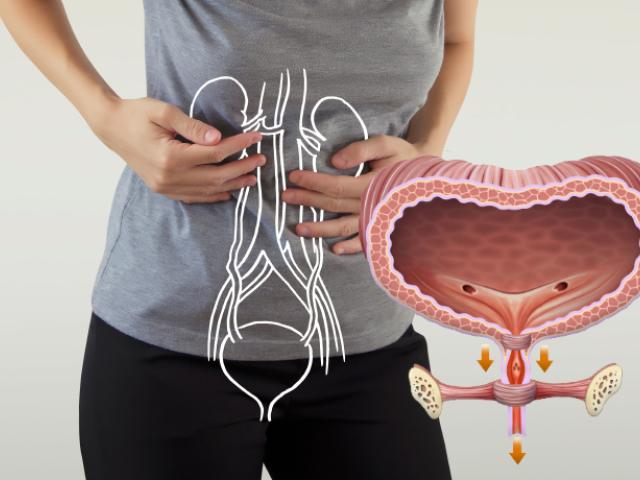

La incontinencia urinaria por estrés ocurre cuando se le escapa la orina repentinamente y de forma involuntaria por un aumento en la presión de la vejiga. Esto podría ocurrir al estornudar, toser o levantar un objeto pesado.